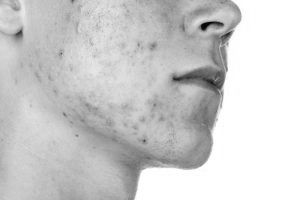

демодекоз - Вугрову хворобу шкіри людини або тварин, яке викликає кліщ Demodex folliculorum (Фолікулярний) і Demodex brevis (Короткий). Це досить неприємне явище, особливо з естетичної точки зору: вугрі, викликана паразитуванням підшкірного кліща вражає переважно шкіру обличчя, але може переходити і на вушну раковину, а також шкіру повік - очної варіант.

Клінічно демодекоз з його проявами зустрічається у представників будь-якої вікової групи, але найчастіше у людей середнього віку і літніх, при цьому на шкірі обличчя виникають фолікулярні папули - вузлики і пустули - бульбашки з гнійним вмістом, які перебувають найчастіше на щоках і асиметрично (одна сторона особи). Паразитування підшкірного кліща супроводжується лущенням шкіри і свербінням, особливо в нічний час.

Клінічно демодекоз може проявлятися в двох формах. Первинний варіант розвивається без видимих пошкоджень шкіри. При вторинному демодекозе висипання носять загальний характер, аж до повної поразки всієї шкіри обличчя. Він виступає як ускладнення на тлі основного захворювання (наприклад, дерматит).